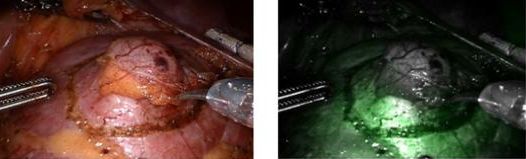

±¹³» ù Çü±¤À̹ÌÁö 4¼¼´ë ·Îº¿¼ö¼ú µµÀÔ

ºÐ´ç¼­¿ï´ëº´¿øÀÌ ÃÖ±Ù 4¼¼´ë ·Îº¿¼ö¼ú ÀåºñÀÎ '´ÙºóÄ¡ Si¸¦ ±¹³» ÃÖÃÊ·Î µµÀÔÇß´Ù. ÀÌ ·Îº¿¼ö¼úÀº Çü±¤ À̹ÌÁö(Firefly)¸¦ Àû¿ë2013-06-25 11:15:17